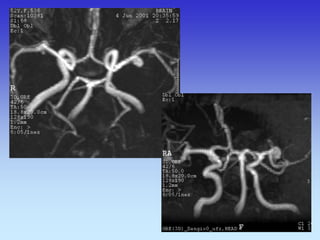

METODE PRIKAZA KRVNIH ŽILA

•UZ-DOPPLER

•DSA

•CTA

•MRA

VASKULARNA OPSKRBA WILLIS-ijev prsten

a. cerebri ant.

a. cerebri media

a. cerebri post.